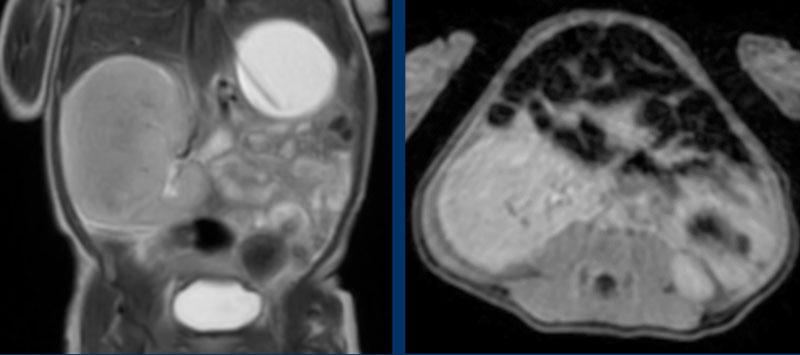

Hình ảnh

Siêu âm và MRI của bé trai bốn tuổi với tổn thương dạng nang đa thùy ở vùng cực giữa thận trái (mũi tên).

Tổn thương được phát hiện tình cờ khi bé được chín tháng tuổi. Trong quá trình theo dõi, không ghi nhận sự thay đổi nào. Tổn thương phù hợp với u thận dạng nang, một tình trạng lành tính.

Tổn thương tương tự được quan sát trên ảnh chuỗi xung T2W mặt phẳng ngang.

Các hình ảnh này thuộc về bé gái một tuổi.

Trên siêu âm, ghi nhận một khối u đa nang với tín hiệu tưới máu ở các vách ngăn.

Hình ảnh chuỗi xung T2W cho thấy rõ hơn phạm vi của tổn thương. Có thể quan sát thấy phần mô thận bình thường còn lại ở cực dưới, giúp phân biệt tổn thương này với thận loạn sản đa nang.

Khối u này được chẩn đoán là u thận dạng nang, và bệnh nhân đã được phẫu thuật cắt thận phải.